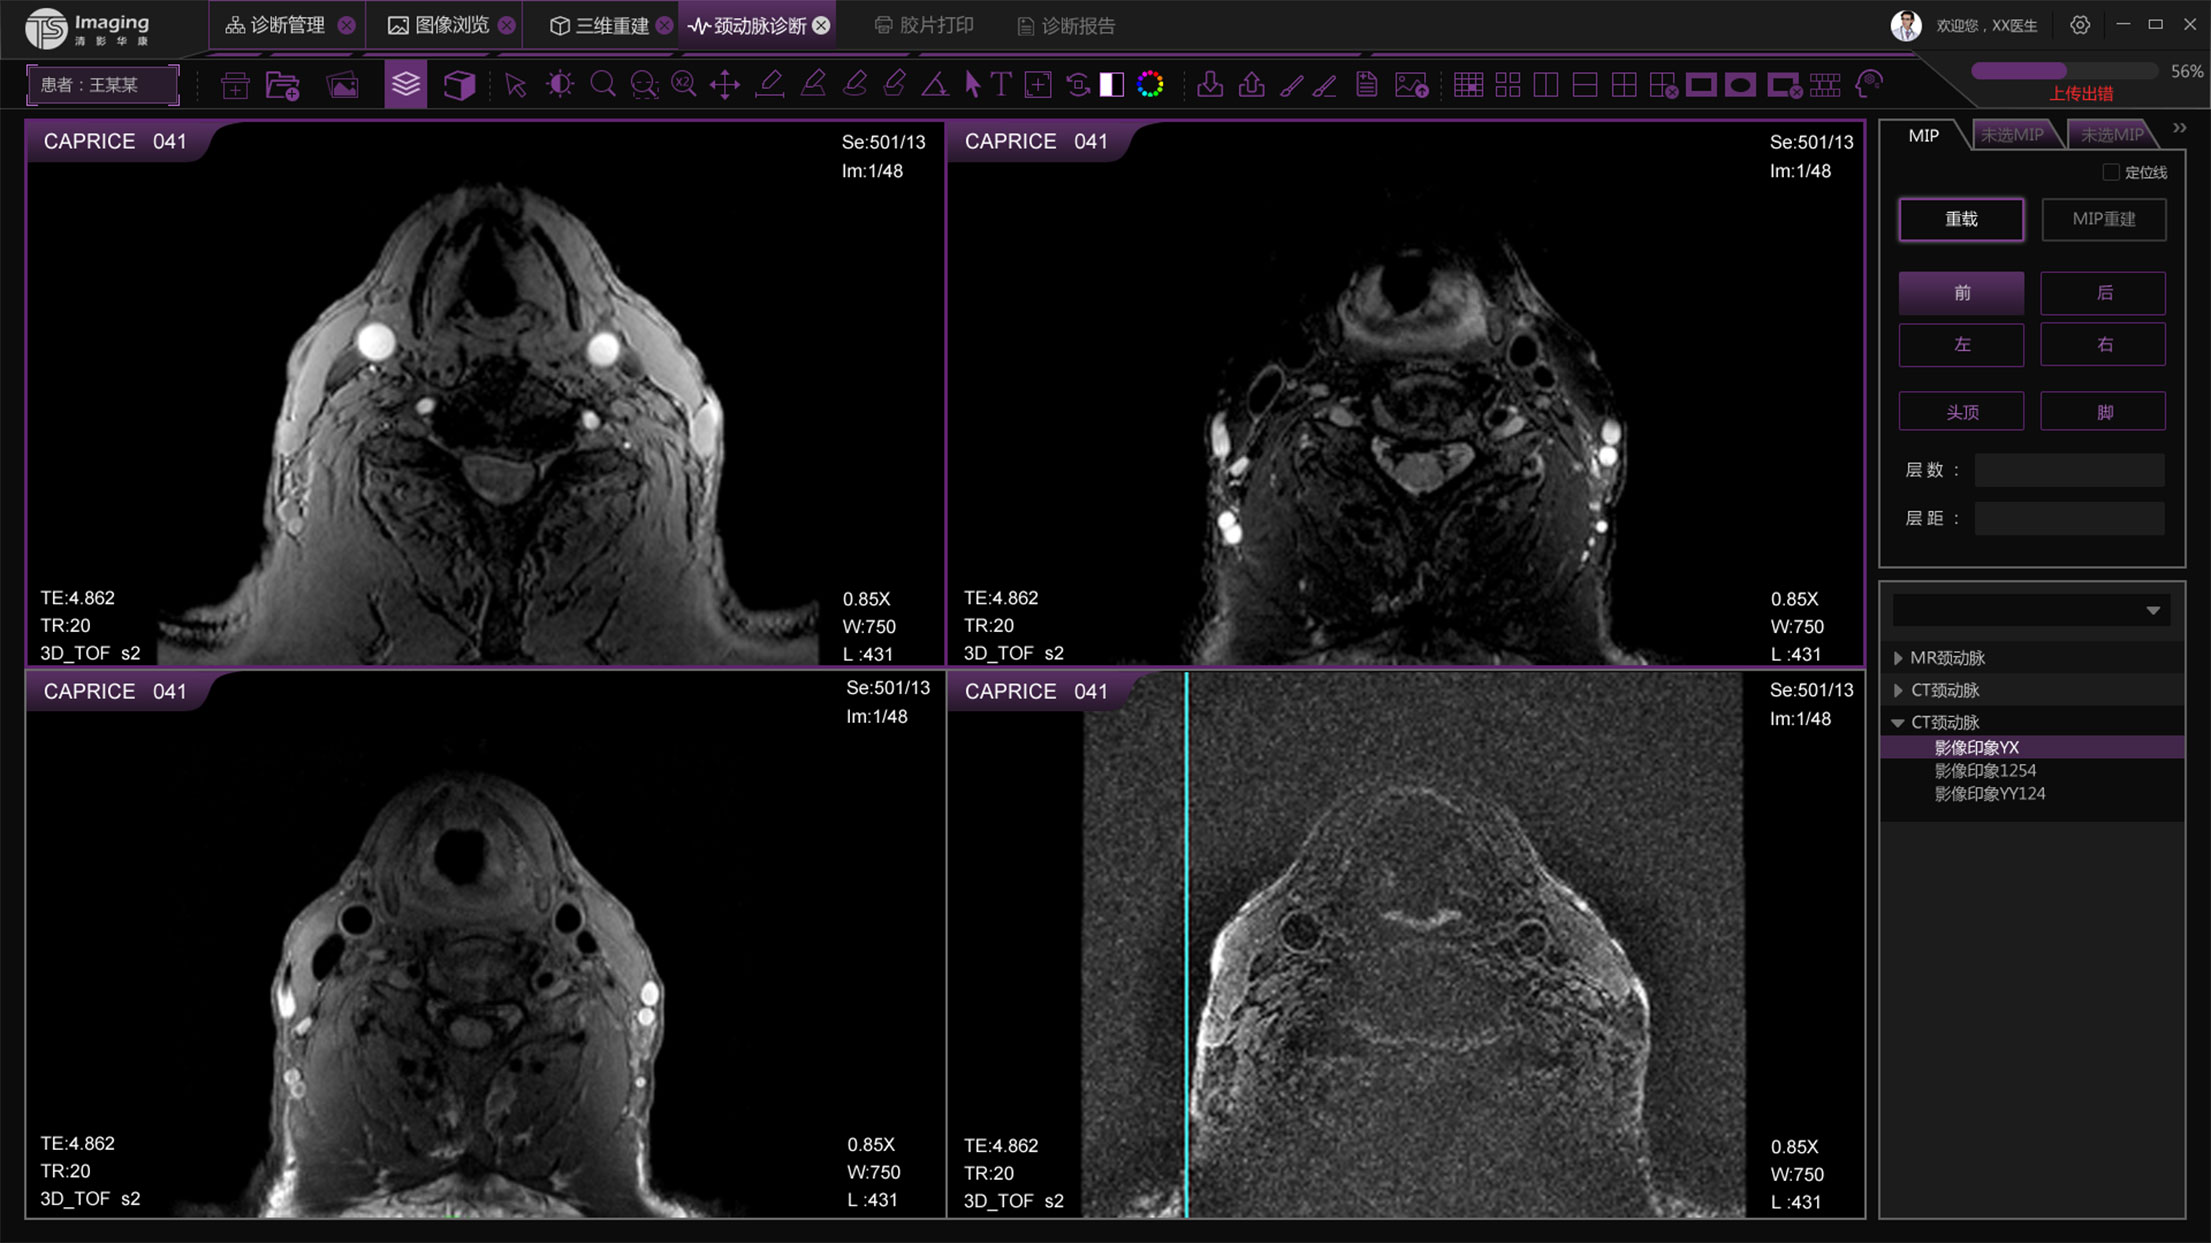

頸動脈診斷頁面

頸動脈診斷頁面整體布局和三維重建比較相似,最大的區別是右側的操作區域,血管分析都為按鍵操作,通過間隔的大小分成三部分。單層切片除了按鍵還有下拉菜單的操作。